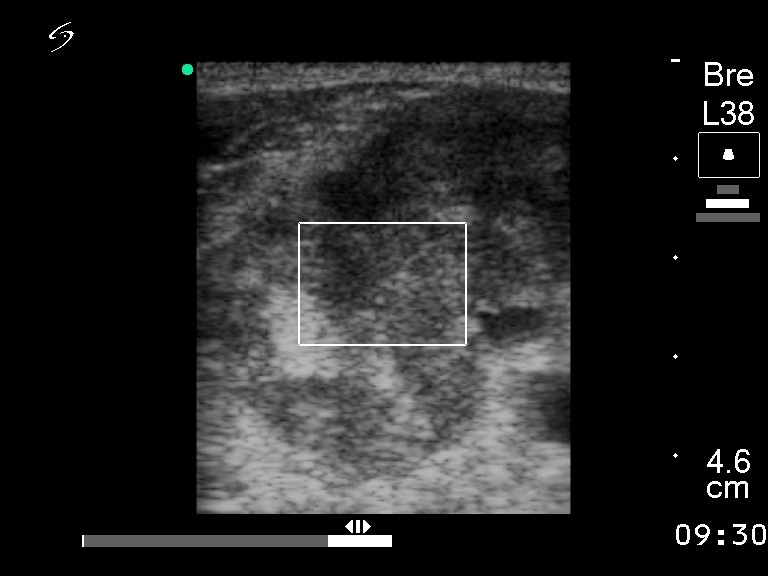

Ultrasonography. The right lobe was enlarged and consisted of multiple hypoechogenic nodules. Multiple enlarged lymph nodes were detected on the right side of the neck.